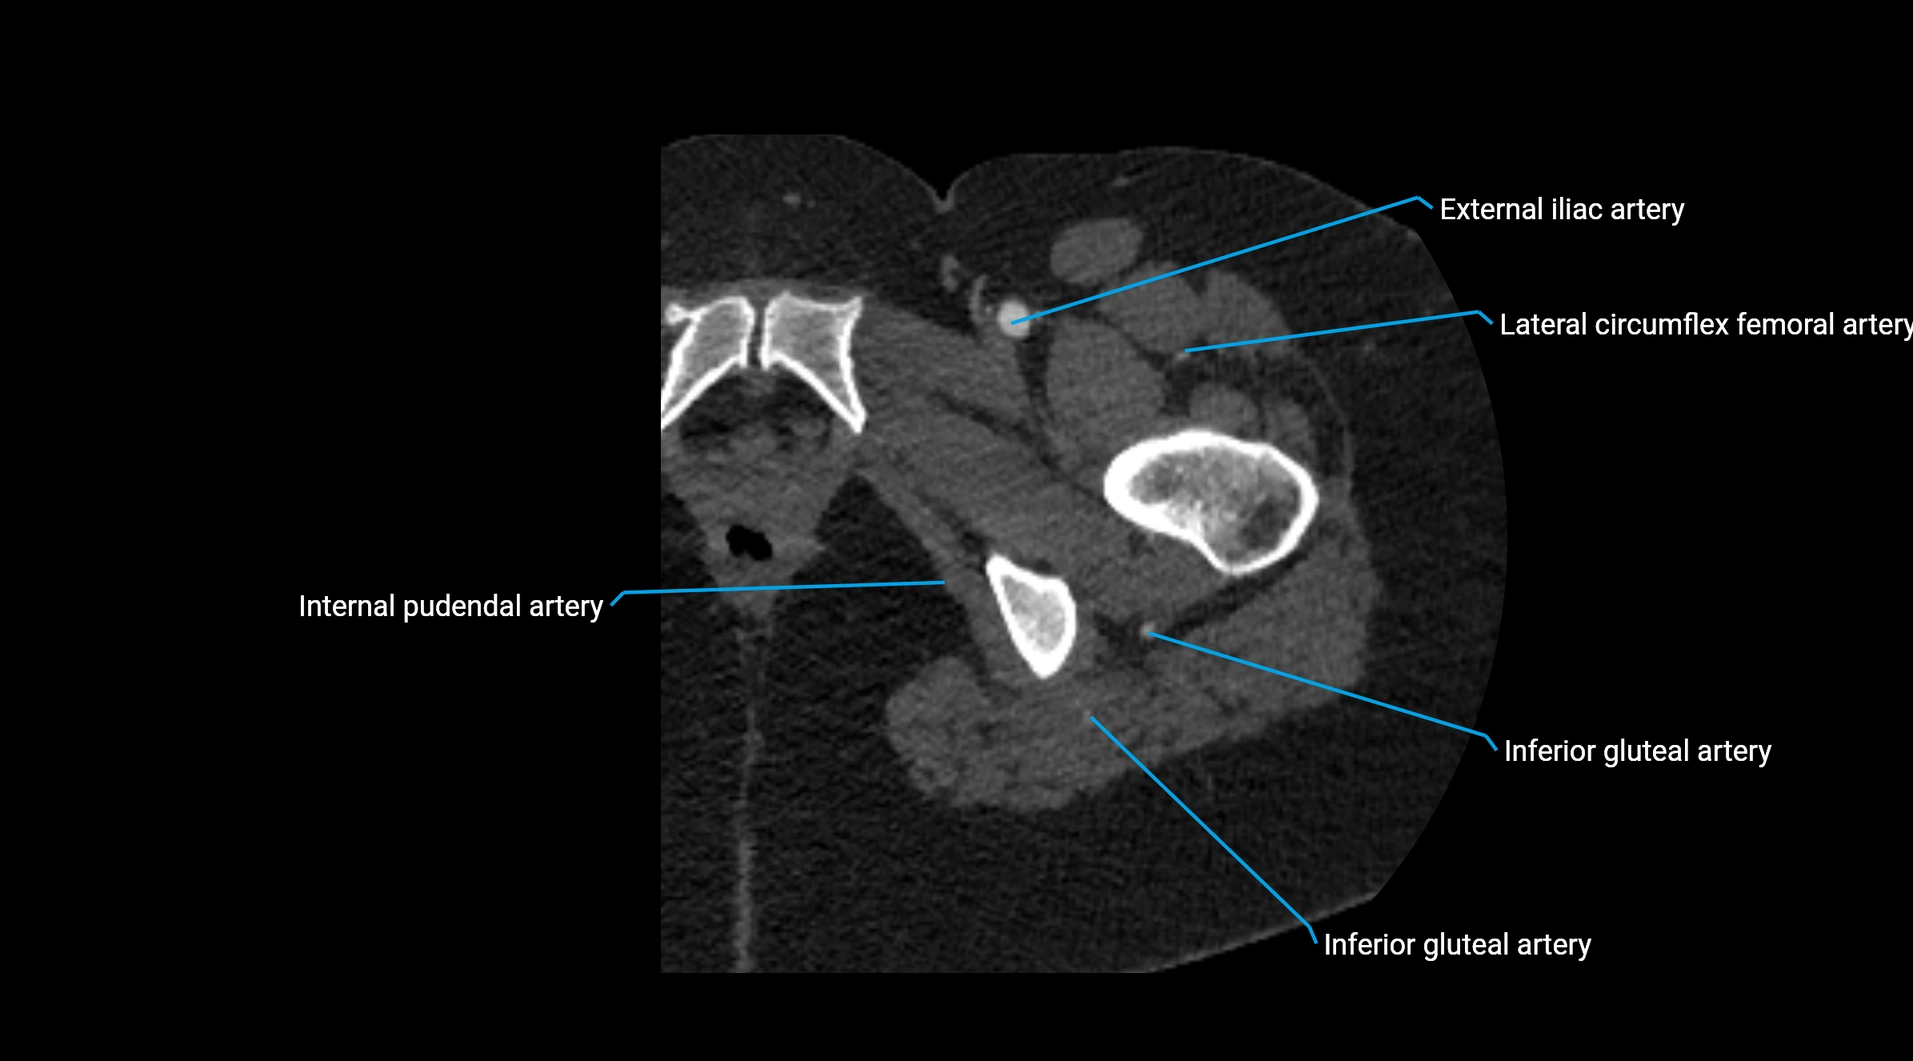

Contrast-enhanced CT (CTA):

• Gold standard for abdominal aortic imaging

• Provides excellent detail of lumen, wall, aneurysm, thrombus, and branch vessels

• Multiplanar and 3D reconstructions help in aneurysm measurement, stent graft planning, and dissection evaluation

• Detects acute rupture, traumatic injury, or occlusion with high sensitivity